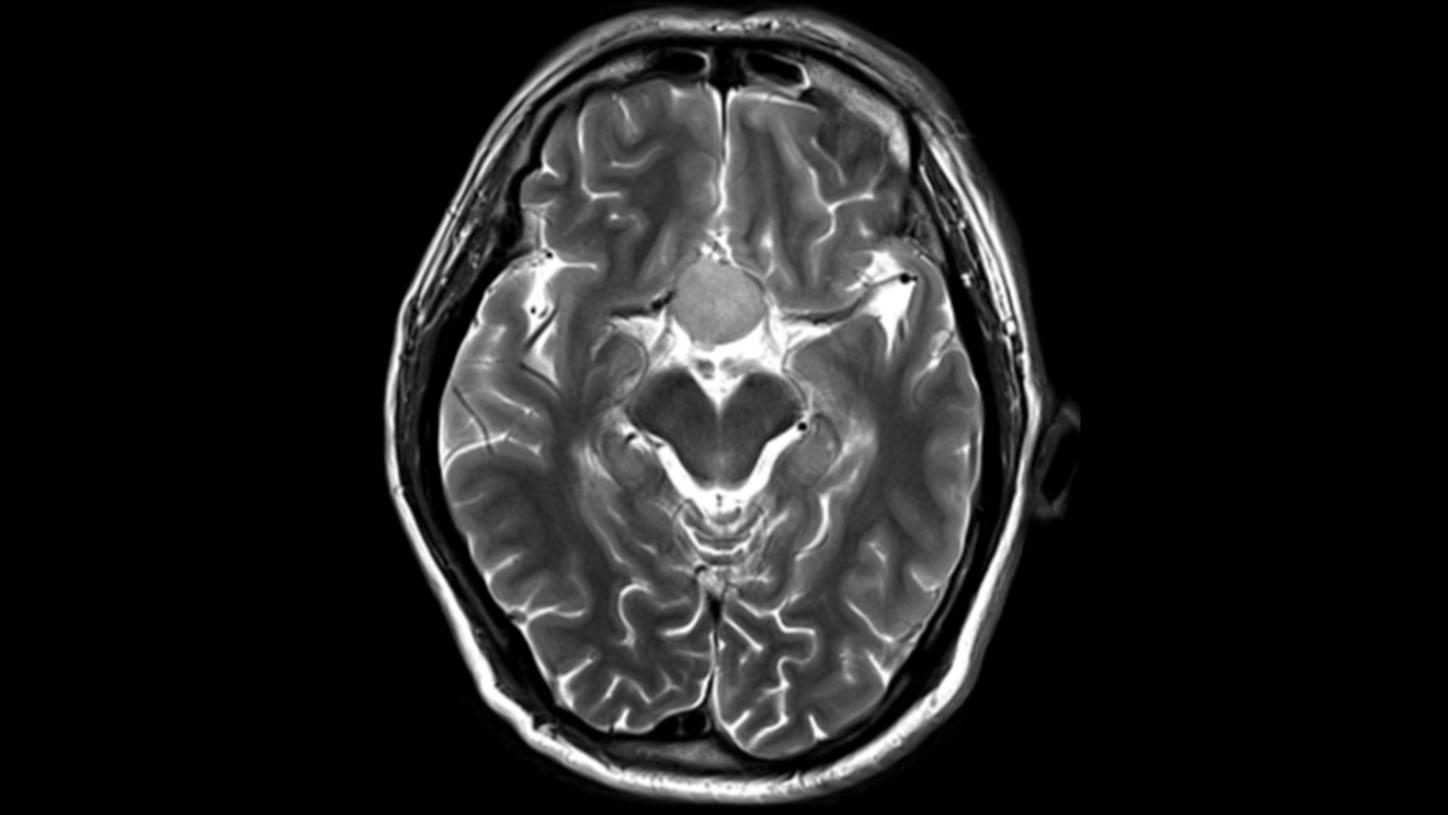

Key investigation areas for MRI are soft tissue areas like brain, abdomen, vessels, ligaments, cartilages or muscles.

Fig.1: Courtesy of Tongji Hospital, Wuhan, China

Key investigation areas for MRI are soft tissue areas like brain, abdomen, vessels, ligaments, cartilages or muscles.